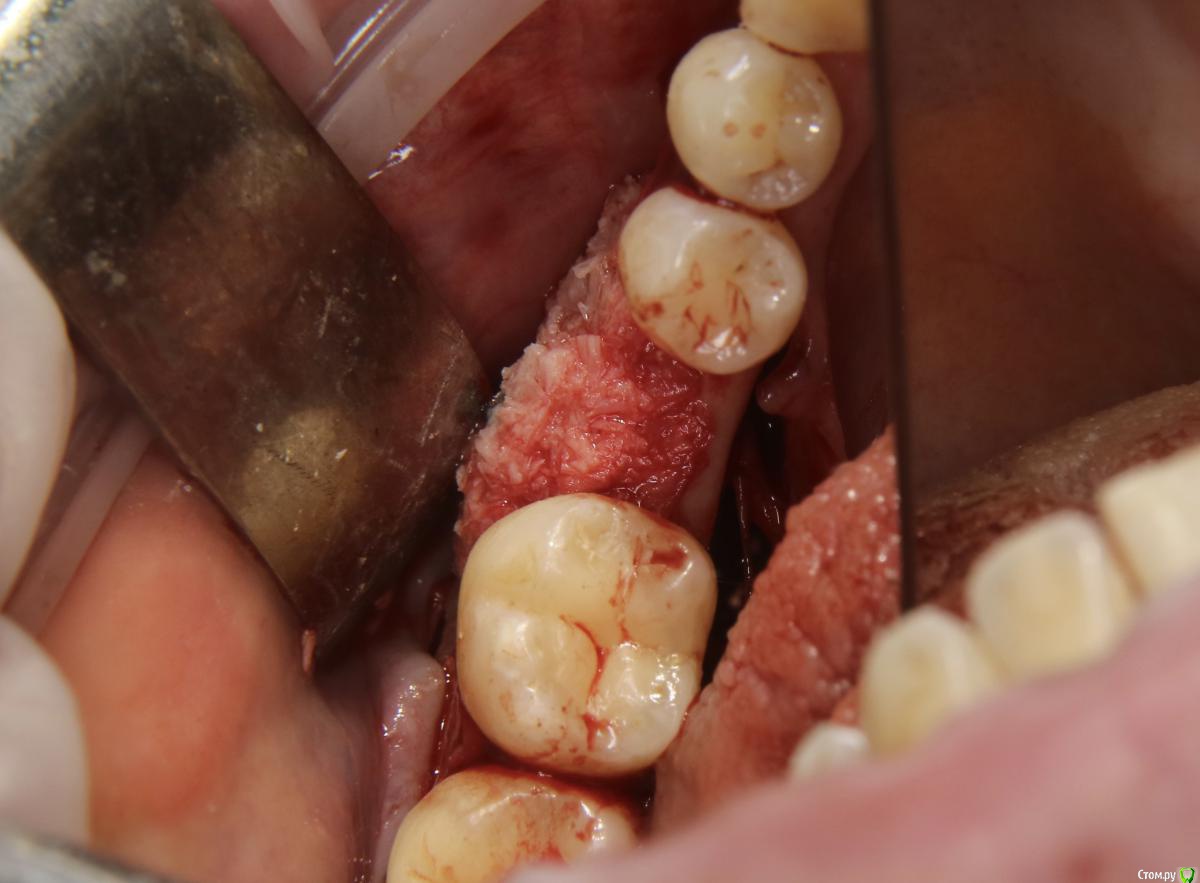

Doctor Vlad Опубликовано 27 августа, 2020 Поделиться Опубликовано 27 августа, 2020 а чем перекрывали аугментат? сопелька? Ссылка на комментарий

Александр07 Опубликовано 30 августа, 2020 Автор Поделиться Опубликовано 30 августа, 2020 а чем перекрывали аугментат? сопелька?Если имеете ввиду Прф то да Ссылка на комментарий

Doctor Vlad Опубликовано 31 августа, 2020 Поделиться Опубликовано 31 августа, 2020 Если имеете ввиду Прф то дада. я название забыл) Ссылка на комментарий